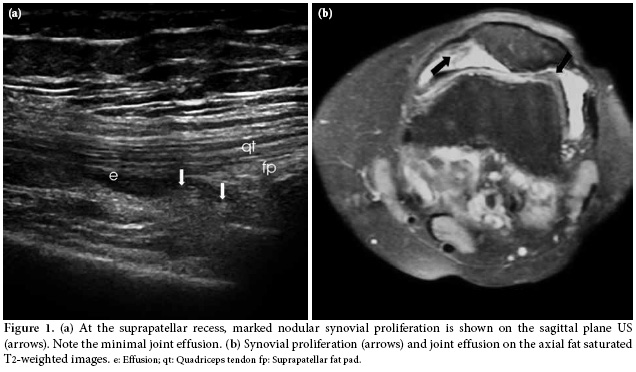

The US examination was performed first with the patient in a supine position in which the knee is flexed approximately 20-30 degrees while supported by a pillow, and the transducer was positioned longitudinally above the patella at the level of suprapatellar recess. The total synovial thickness and anteroposterior diameter of the suprapatellar bursa were measured. The synovial proliferation was considered positive when the total synovial thickness was above 3 mm, and the effusion was considered positive when it was 5 mm or higher (Figure 1a, b). During the longitudinal scan at the level of the suprapatellar recess, special attention was paid not to compress the recess. In the evaluation of the synovial proliferation, any presence of vascularization as a supporting evidence was evaluated with the color mode of the power Doppler US (Figure 2). However, because the study aimed to compare the B mode US findings and MRI findings and no contrast material was used in the MRI evaluations, spectral analyses and/or comparisons could not be made. In the same position, the patellar and quadriceps tendons were examined, and tendonitis was diagnosed if the thickness was increased and blurring and heterogeneous hypoechogenecity were differentiated.